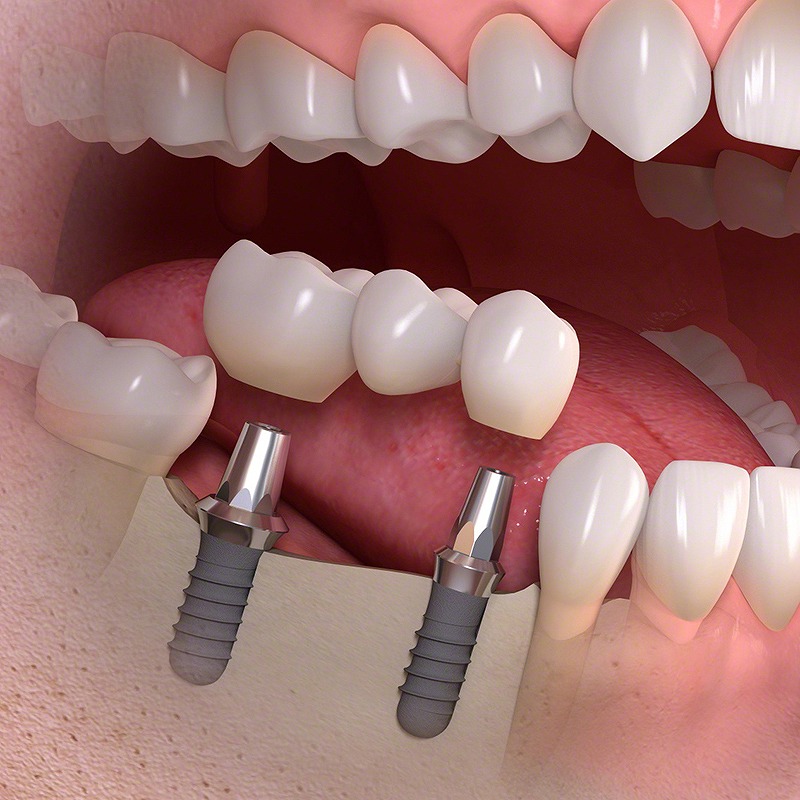

インプラント治療とは、歯を失った部分に人工の歯根を埋め込み、その上に人工歯を取り付ける治療法です。顎の骨に結合することでよく噛めるうえに、審美性に優れた人工歯を使用するため美しい口元を取り戻すことができます。

インプラント治療とは、歯を失った部分に人工の歯根を埋め込み、その上に人工歯を取り付ける治療法です。顎の骨に結合することでよく噛めるうえに、審美性に優れた人工歯を使用するため美しい口元を取り戻すことができます。

インプラントの構造

インプラントは、次のパーツで成り立ちます。

インプラントは、次のパーツで成り立ちます。

- インプラント体(顎の骨に埋め込む人工の歯根)

- アバットメント(インプラント体と人工歯をつなげるための連結器具)

- 人工歯

インプラント体は生体親和性に優れたチタンかチタン合金を使用しており、金属アレルギーが起きる心配はほとんどありません。チタンのアレルギーがある方も一度ご相談ください。